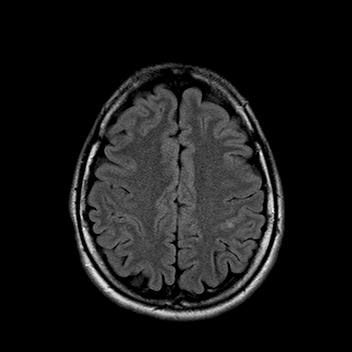

При сканировании головного мозга в нескольких режимах в кортикальных отделах левой теменной доли был обнаружен лакунарный инфаркт диаметром 7мм. Острый инфаркт хорошо виден на ДВИ (импульсная последовательность, доступная в томографах экспертного класса), но плохо виден в режиме с подавлением сигнала от свободной жидкости.

После проведенного лечения состояние пациентки улучшилось. На МР-томографии спустя 3 месяца заметна положительная динамика.